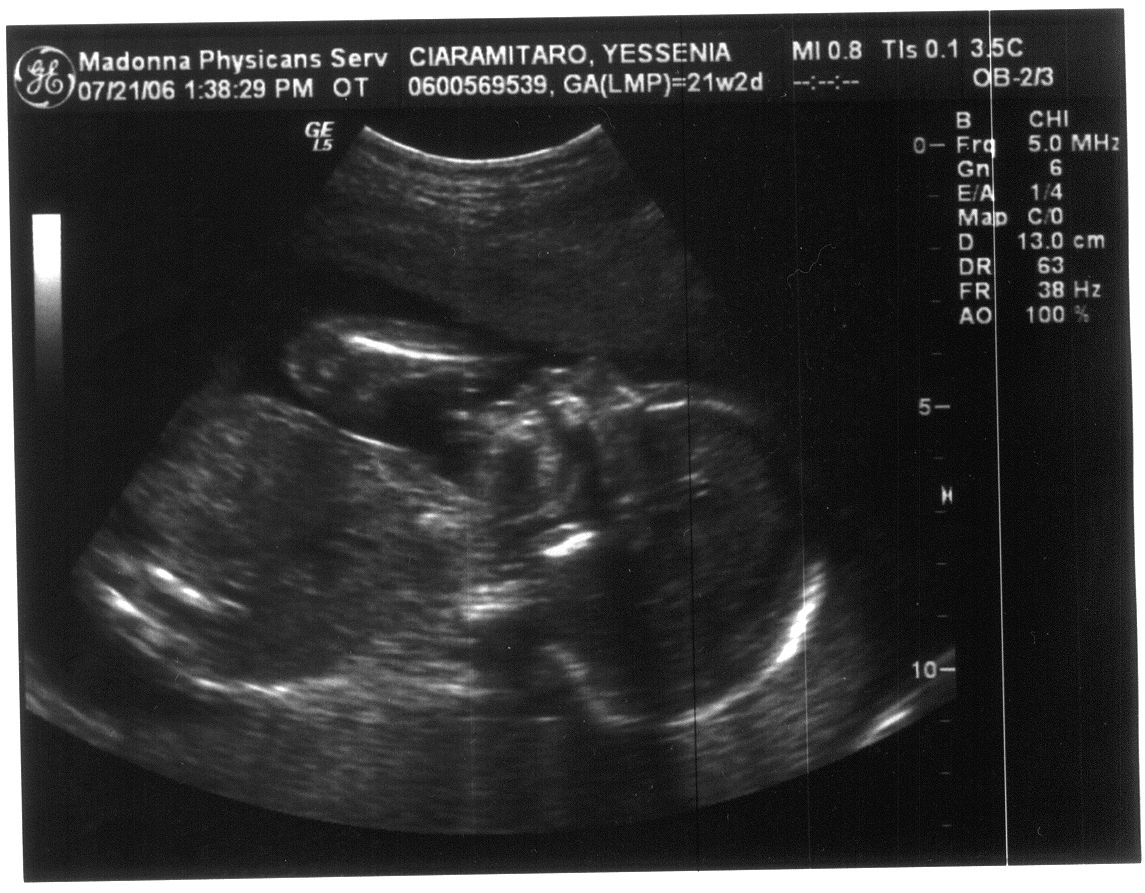

Last Modified On:March 2, 2015 5 PM Welcome to the future member of the Ciaramitaro clan!

Looks like our baby is coming bundled with a Skeleton Halloween Costume!